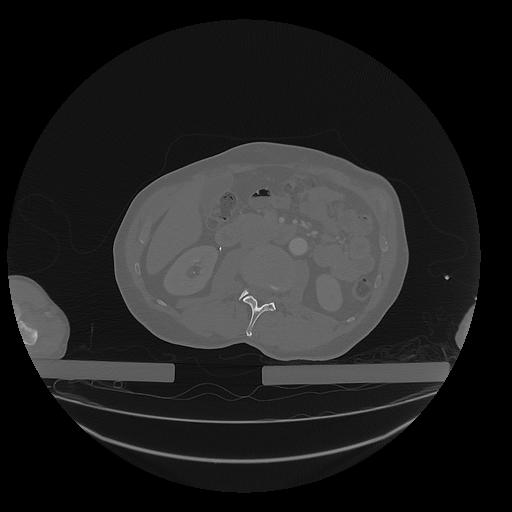

31 PULMON,CE,Vol,1.0,PULMON,,